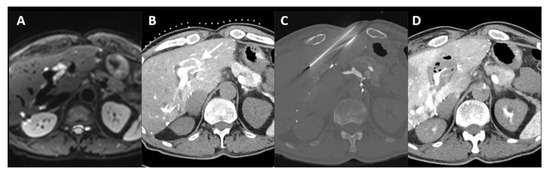

| 1 | 20 mm | Common hepatic artery | 15–20 mL Visipaque™ | Emprint™ Microwave Ablation System, Medtronic-Covidien, Boulder, CO, USA | MD Anderson, Houston, TX, USA |

| 2 | 20 and 7 mm | Common hepatic artery | 4 mL Xenetix 300® | Cool-tip™ RFA Ablation Aystem, Medtronic-Covidien, Boulder, CO, USA | Gustave Roussy, Villejuif, France |

| 3 | 12 mm | Left-sided hepatic artery | Not specified | Cool-tip™ RFA Ablation System | Gustave Roussy |

| 4 | 9 mm | Common hepatic artery | 10 mL Xenetix 300® | Emprint™ Microwave Ablation System | Amsterdam UMC, Amsterdam, The Netherlands |

| 5 | 15 mm | Coeliac trunk | 20 mL Xenetix 300® | Emprint™ Microwave Ablation System | Amsterdam UMC |

| 6 | Not applicable | Common hepatic artery | 20 mL Xenetix 300® | Emprint™ Microwave Ablation System | Amsterdam UMC |

| 7 | Confluent | Common hepatic artery | 10 mL Xenetix 300® | NanoKnife system under ECG-gating; AccuSync model 72, AngioDynamics, Latham, NY, USA | Amsterdam UMC |

| 8 | 15 mm | Common hepatic artery | 15–20 mL Visipaque™ | Emprint™ Microwave Ablation System | MD Anderson |